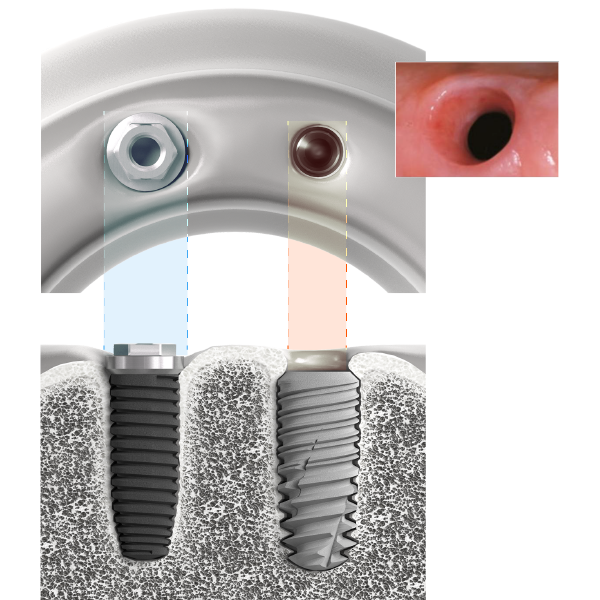

A l’origine considérée comme une solution essentiellement fonctionnelle, la prothèse implanto-portée trouve aujourd’hui pleinement son indication dans les restaurations esthétiques du secteur antérieur

Immédiatement visibles lors du sourire, les restaurations à visée esthétique constituent un défi majeur car elles doivent prendre en compte non seulement les tissus dentaires environnants (émail et dentine), mais aussi les tissus parodontaux (os et gencive) dont la prévisibilité peut être très relative. Le défi esthétique est d’autant plus complexe que le succès de ce type de restauration est soumis à la subjectivité du patient. Néanmoins, la reconstruction des papilles, l’alignement des collets, le choix des bons matériaux et le maintien de la santé parodontale sont autant de critères universels à prendre en compte afin d’évaluer la reproductibilité et la pérennité des techniques opératoires mises en œuvre.